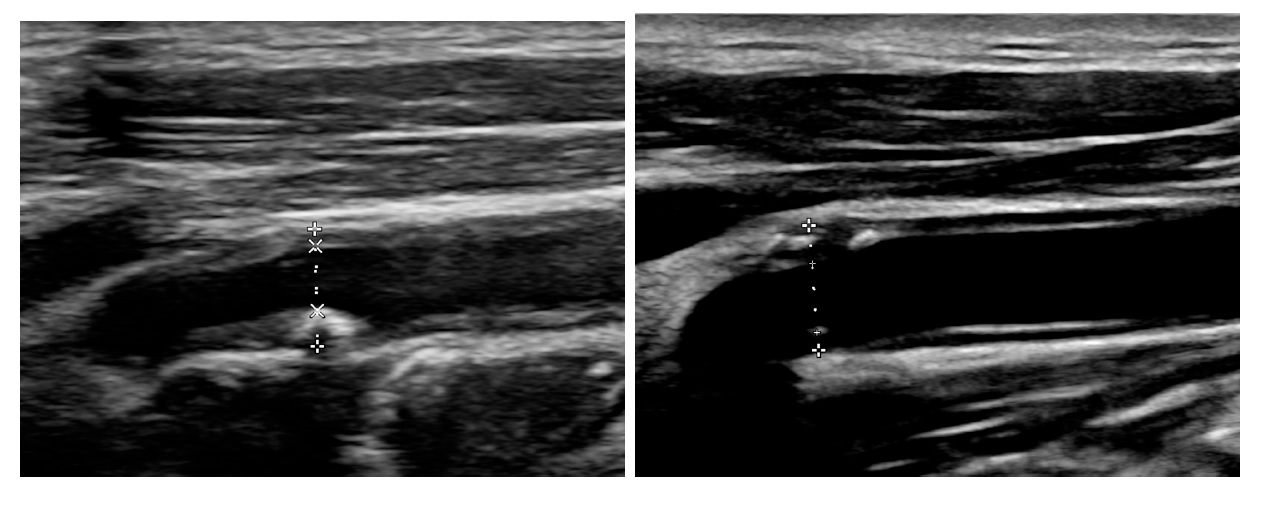

在影像比對中,2022年仍見顯著斑塊;經持續使用降血脂藥物,今年追蹤影像顯示,頸動脈斑塊體積明顯減少、血管壁恢復光滑,血流更為順暢,治療獲得良好成效。積極控制血脂肪為臨床上醫師常常進行的決策處方,也符合國際治療指引,只是常常沒有機會讓一般民眾看到其治療成果。